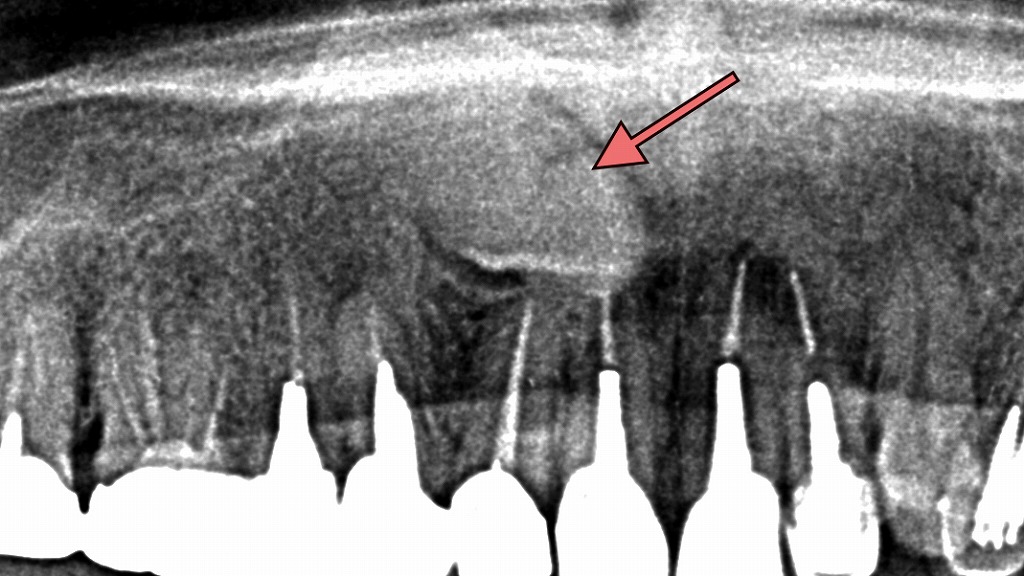

犬歯が埋伏歯となったレントゲン画像

この画像は、上顎のパノラマレントゲン画像です。

赤い矢印で示された部分に、犬歯(けんし/糸切り歯)が骨の中に埋まっている様子が確認されます。

以下に詳しく解説します👇

🦷 犬歯の埋伏歯とは

犬歯は本来、側切歯(前から2番目の歯)と第一小臼歯(前から4番目の歯)の間に生える歯です。

しかしこの画像では、犬歯が**骨の中に埋まったまま生えていない「埋伏歯(まいふくし)」**の状態にあります。

⚠️ この状態で起こりうる問題

- 隣の歯の歯根を圧迫して歯根吸収を起こすことがある

- 歯列の乱れや審美的な不整

🩺 対応・治療の方向性

犬歯は噛み合わせや審美性において非常に重要な歯です。

そのため、以下のような治療方針が検討されます。

- 矯正的牽引(けんいん)

→ CTで位置を確認し、矯正装置で少しずつ歯を引き出す方法。 - 外科的抜歯

→ 正しい位置に導出が難しい場合や嚢胞を伴う場合に行われます。 - 経過観察

→ 症状がなく、隣接歯への影響がない場合には定期的にレントゲンで確認。